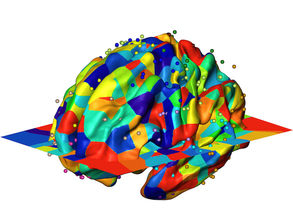

Genes to Brains